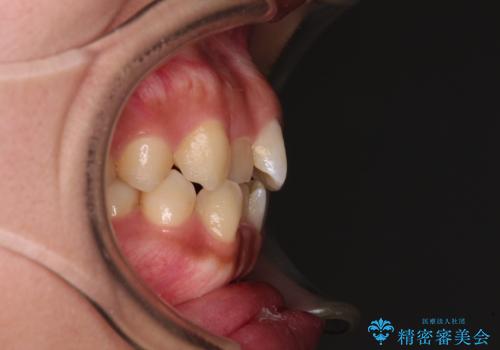

- 前歯のデコボコと口元の突出感を気にして来院された患者様です。

非抜歯矯正ではデコボコを解消することでより口元が突出してしまうため、上下左右の小臼歯4本の抜歯を行い、ワイヤー装置による矯正治療を行うこととしました。